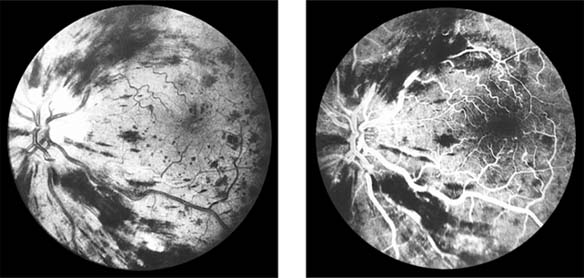

In anterior segment ischemia, patients develop iritis, intraocular pressure changes, and pupillary abnormalities. In retinal ischemia (Figure 15-12A), patients show evidence of capillary dilation and hemorrhages, capillary occlusion, new vessels at the optic disk, and cotton-wool spots.

Figure 15-12

Figure 15-12: A: Fluorescein angiogram of left fundus in a patient with chronic ocular ischemia secondary to Takayasu's disease. Note capillary dilation, leakage of dye, retinal hemorrhages, cotton-wool spots, and neovascularization of the optic nerve head. B: Fluorescein angiogram, showing leakage at optic disk and macula in a patient with chronic ocular ischemia secondary to dural arteriovenous fistula.

Carotid Cavernous Fistula